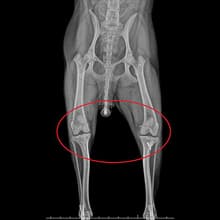

엑스레이2살 비숑프리제 : 슬개골탈구 수술

2살 비숑프리제가 옥길아라동물치료센터에 내원했습니다. 처음 내원할 때, 아이가 잘 걷지 않으려고 해서 병원에 내원해주신 경우입니다. 정확한 확인을 위해 정형 검사와 영상 검사를 진행하였습니다. 꼼꼼한 검사 결과 우측 슬개골 탈구3기와 좌측 슬개골 탈구 2기로 진단되었습니다. 엑스레이 검사 상으로 양측 슬개골이 내측으로 변위되었고, 우측의 변위가 더 심했습니다. 보행에 큰 불편함이 확인된 상태로 수술적 치료가 필요한 상황이었습니다. 수술은 증상에 따라 다른 수술 방법이 적용됩니다. 옥길아라동물의료센터 의료진은 정밀한 수술과 예후 관찰을 진행하였습니다. 양측 대퇴골 활차구 성형과 슬개골 탈구 3기에 해당하는 우측은 경골 조면 이식술을 병행 적용키로 결정하여 수술을 진행하였습니다. 수술 경험이 풍부한 외과 전담 선생님과 전문 의료진이 아이의 수술을 전담 진행하였고, 수술 후에는 빠른 회복을 재활치료를 진행해 주었습니다. 수술 후 2일차부터 염증 수치는 안정화되었고, 3일차 부터 잘 걷게 되어 무사히 보호자님께 인계되었습니다.

슬개골 탈구 수술은 증상에 따라 다른 수술 방법이 적용됩니다. 옥길아라동물의료센터 의료진은 정밀한 수술과 예후 관찰을 진행합니다.